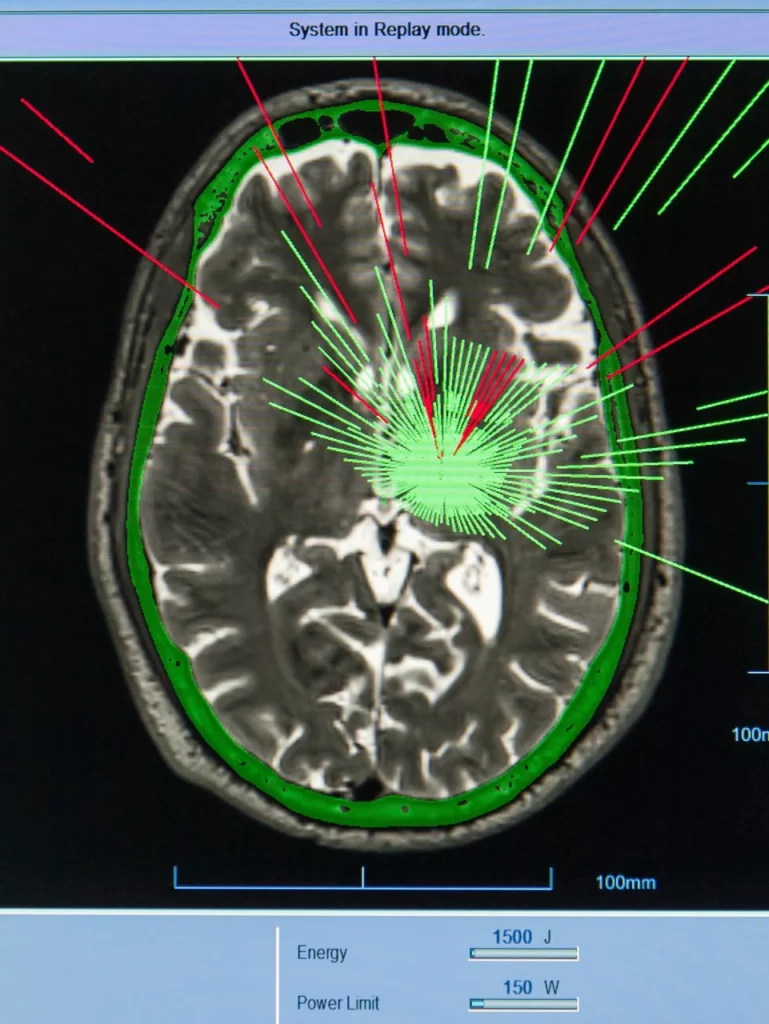

Uno de los avances más prometedores para reducir los síntomas del Párkinson es el Ultrasonido Focalizado de Alta Intensidad (HIFU, por sus siglas en inglés), una técnica no invasiva que utiliza energía ultrasónica guiada por resonancia magnética para intervenir áreas específicas del cerebro sin necesidad de abrir el cráneo ni recurrir a anestesia general.

Este procedimiento se enfoca principalmente en dos núcleos cerebrales: el tálamo, para reducir temblores, y el subtálamo, que también mejora la rigidez y la torpeza motora.

El monitoreo en tiempo real por resonancia magnética permite una precisión milimétrica, dirigiendo la energía únicamente a las áreas afectadas.